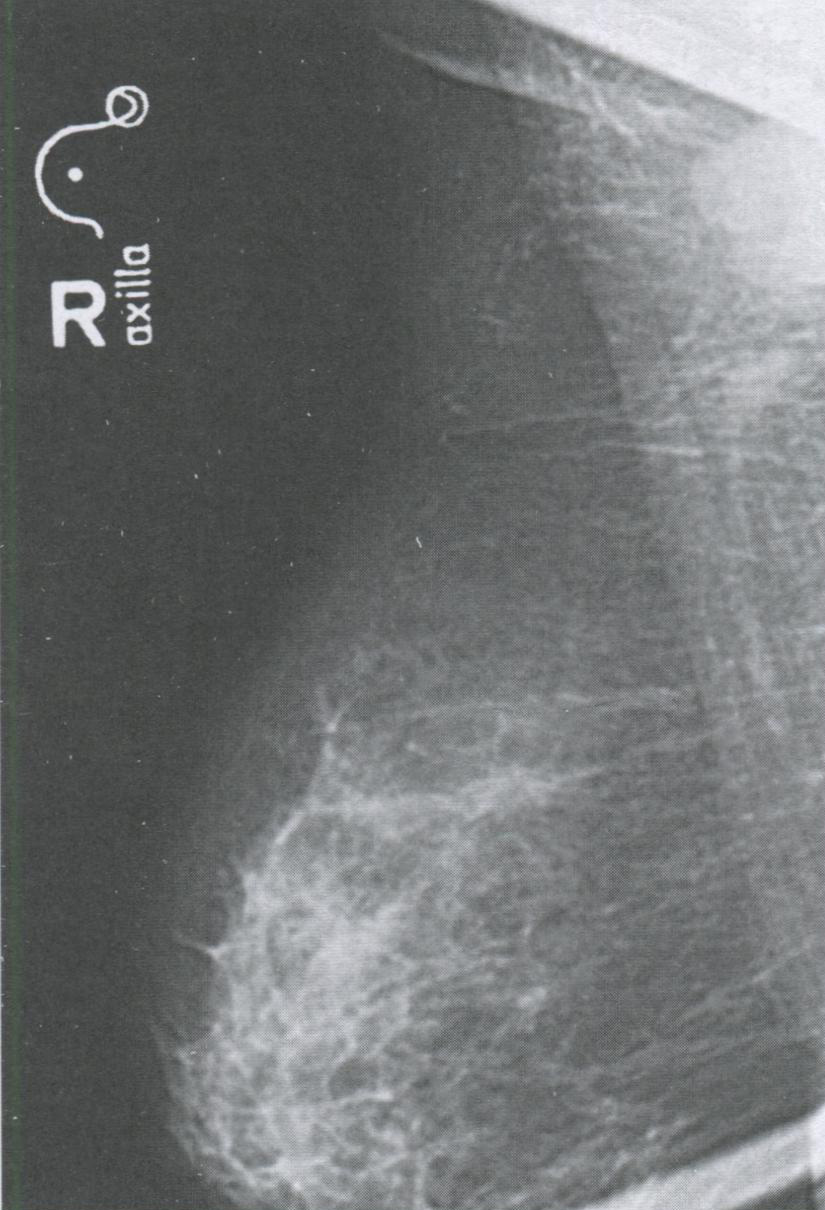

Рис. 3.8. Рентгенография мягких тканей подмышечных областей

Рентгенография мягких тканей подмышечных областей